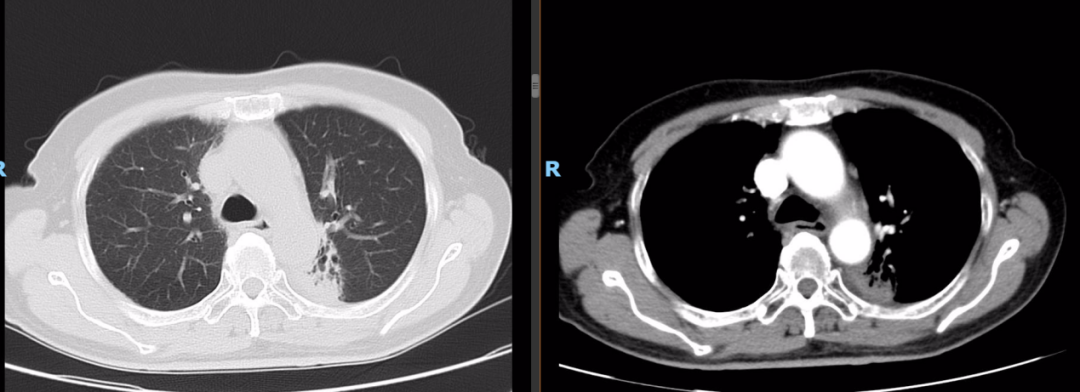

胸部平扫+增强CT(2020-08-27):食道中段管壁增厚,上下累及约4.5厘米(约胸5/6椎间隙水平至胸8椎体上缘水平),增强后可见轻度强化,隆突下见境界不清淋巴结。左肺上叶尖后段及相邻左肺下叶背段交界处见团块状直径约2.5厘米软组织密度灶,边缘可见毛刺,左侧胸腔积液,左下肺膨胀不全。右肺下叶见少许条状影。结论:1、食管癌。2、左肺上叶尖后段病灶,符合肺癌。左侧胸腔积液,左下肺膨胀不全。

病理结果:(肺占位组织)见癌组织浸润,结合免疫组化结果,病变为肺浸润性腺癌。免疫组化:CK7(+)、TTF-1(+)、NapsinA(+)、Syn(-)、P63(个别细胞+)、P40(-)。

肺癌组织NGS结果:1、MET基因c.3028+1G>T第14外显子跳读突变,组织丰度:7.5%,FDA批准药物:克唑替尼、卡马替尼、特泊替尼等靶向治疗。2、未检测到MSI-H。3、未检测到ALK、BRAF、BRCA、EGFR等突变。

同时性食管、肺双原发癌(食管鳞状细胞癌cT3N0M0 IIb期;左肺腺癌cT3N0M0IIb期,MET基因跳跃突变阳性)